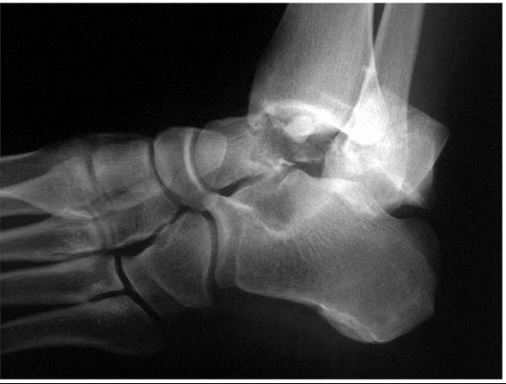

A 29-year-old male sustains the isolated lower extremity injury shown in Figure A. During open reduction, what structure must be kept intact in order to protect the remaining blood supply to the talar body?

This is a Hawkins 3 talar neck #

critical to preserve the deltoid ligament because the deltoid branch of the PT, which supplies the medial half of the talar body, is the only remaining blood supply.